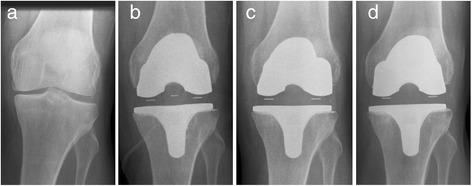

Thirty-eight primary total knee arthroplasties (TKAs) were performed on 34 patients using the metal-free BPK-S ceramic total knee replacement system with both the femoral and tibial components of an alumina/zirconia ceramic composite. The clinical outcome was evaluated pre- and postoperatively at 3 (n = 32 TKA) and 12 months (n = 32 TKA) using the Knee Society Score (KSS), the Oxford Knee Score and the EQ-5D. Safety analysis was performed by radiological examination and assessment of adverse events.

Postoperatively, the KSS, Oxford Knee Score and EQ-5D improved significantly at 3 and 12 months (p < 0.001). Non-progressive partial radiolucent lines were observed in six cases, but there was no osteolysis and no implant loosening. Induction or exacerbation of allergies did not occur during the follow-up.

The metal-free BPK-S ceramic total knee replacement system proved to be a safe and clinically efficient alternative to metal implants in this short-term follow-up study.